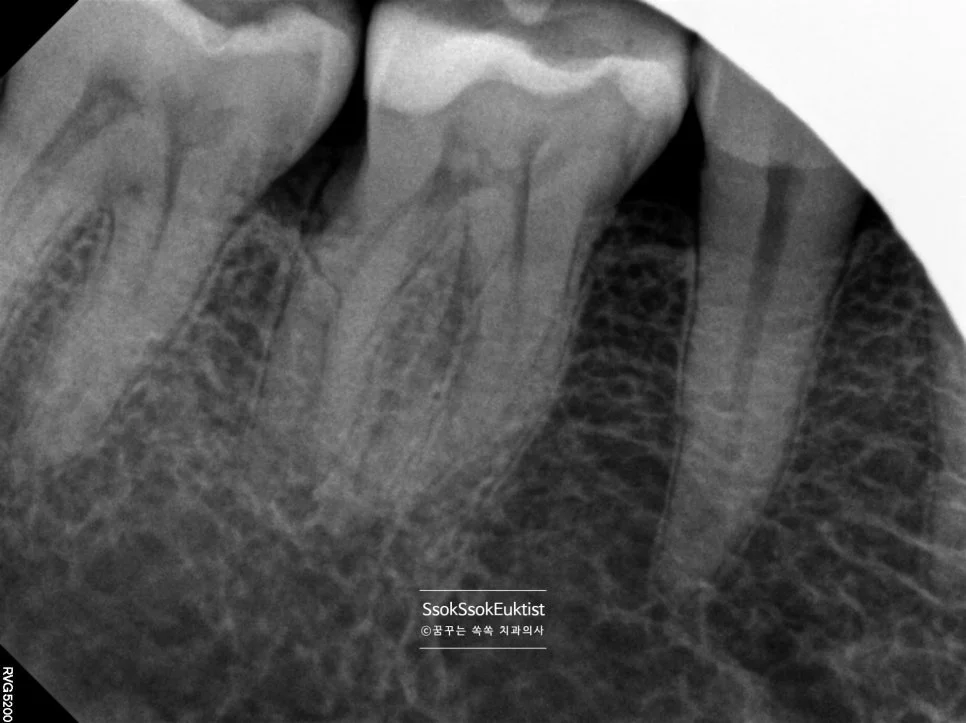

재신경치료 후기와 비용, 발치 판정 치아도 살릴 수 있을까?

치근단 엑스레이 뿌리 끝 검은색 음영 염증 소견

좋은 진료를 정직하게 | 선한 영향력으로 더 나은 가치를 재신경치료 후기와 비용, 발치 판정 치아도 살릴 수 있을까? 강서구 마곡 서울쏙쏙치과 꿈꾸는 쏙쏙 치과의사 박상억입니다^^ 안녕하세요^^ 오늘은 신경치료 후 통증에 의한 재신경치료에 대해 알아볼 건데요^^ 신경치료를 한 지 한참 지난 치아가 어느 순간부터 불편하고 아프다면 오늘의 포스팅이 도움이 되실 거라 생각합니다~^^ 그럼 바로 시작해 보겠습니다! … 더 읽기